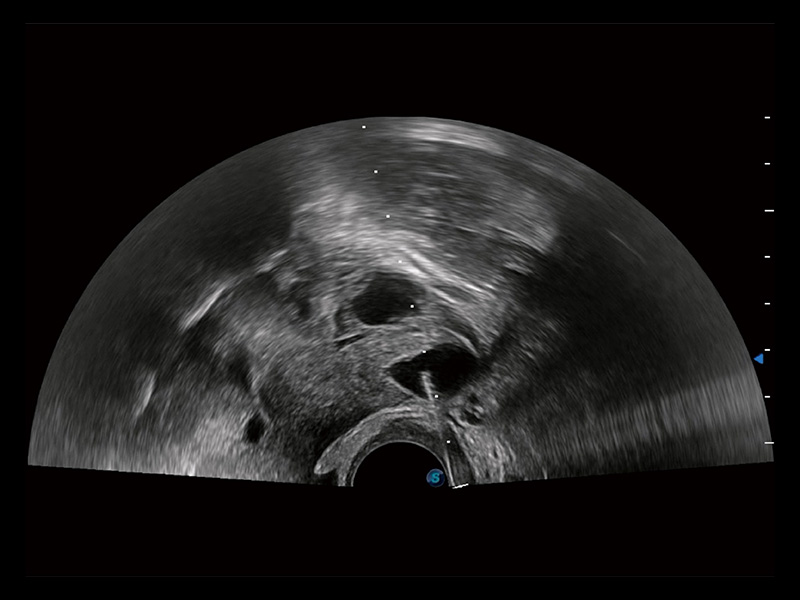

“生育问题”即关系民族复兴,也关系亿万家庭的幸福。随着婚育年龄推迟、社会压力增加等因素,越来越多人群也面临着“生不出、生不好”的问题。辅助生殖作为治疗不孕不育最有效的方法之一,也逐渐成为育儿新希望。而超声检查能为生殖需求人群的初诊评估提供宝贵的信息。 P20 Elite是db真人体育官网匠心打造的一款生殖应用型彩超。她继承db真人体育官网高端极光平台,突破性地将多款新型芯片及硬件模块进行整合,均衡了高端系统性能与小巧灵动机身。P20 Elite卓越的图像质量搭载专科探头,旨在为您提供全面的辅助生殖解决方案。

P20 Elite配备了丰富的生殖探头群和临床应用功能,在卵泡监测、穿刺取卵、胚胎移植、妊娠确认等领域,为生殖需求人群提供了新的临床机会,重新定义高端超声如何应用于生殖健康检查。